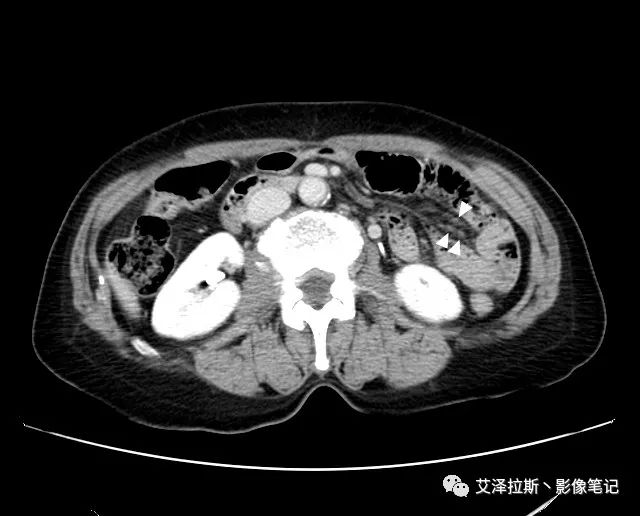

【影像所見】 胃竇部狹窄,胃壁環形增厚,小彎側見一巨大潰瘍,周圍伴“環堤征”,漿膜面不完整,胃周脂肪見網格狀條索影,病灶與肝臟左葉、胰腺鉤突脂肪間隙消失,增強掃描病灶明顯強化。引流區內約15個區域淋巴結受累。

【診斷意見】 胃竇部胃癌(T4N3期) 該病例腫塊突破漿膜層,與肝臟左葉、胰腺鉤突分界不清,脂肪界面消失,定為T4期; 受累及的淋巴結為15個區域,定為N3; 有無遠處轉移尚不明確,所以M期暫時無法確定。